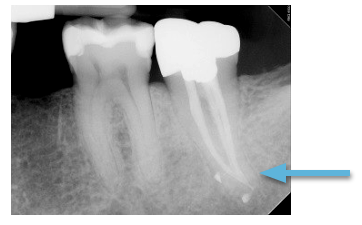

The patient returned for one year follow-up without complaint of pain/swelling. A crown was placed by the general dentist soon after completion of the root canal treatment. Complete healing is evident, with osseous fill and the re-establishment of a normal PDL space and lamina dura.